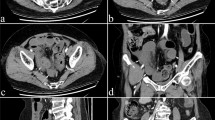

In each specimen, the mesentery of two standardised 40-cm lengths of bowel was dissected to expose the mesenteric arteries; the jejunal segment extended from 20 to 60 cm distal to the duodenojejunal flexure and the ileal segment from 20 to 60 cm proximal to the ileocaecal junction (Fig. 1). The following were recorded in each 40-cm length of jejunum and ileum in all ten specimens: the length of the mesentery (from the SMA to the mesenteric border of the mid-portion of bowel); the length of all jejunal and ileal parent arteries (branches from the SMA to the first arterial arcade); the total number of complete anastomotic rings within the arcades; the total number of arteriae recta. Each 40-cm length of jejunum and ileum was then divided into a proximal and distal section (each measuring 20 cm in length), and two further measurements were made: the minimum and maximum number of tiers of arterial arcades passed through in a straight line from the SMA to the bowel and the length of ten randomly selected arteriae recta (Carbon Fiber Composites Digital Caliper, Ted Pella, Inc., Texas; accuracy ±0.2 mm). All measurements of arterial arcades and arteriae recta were repeated blindly in two specimens by two investigators (DL and MDS) to assess intra-observer and inter-observer variability.

Table 3 summarises the data on the relative muscularity of the jejunal and ileal PA, first arcade artery and AR. There was no statistically significant difference between the muscularity index (proportion of arterial CSA occupied by the tunica media) of proximal jejunal versus distal ileal arteries or among parent, first arcade and AR arteries within the proximal jejunum and distal ileum. A typical sequence of jejunal arteries is shown in Fig. 4.